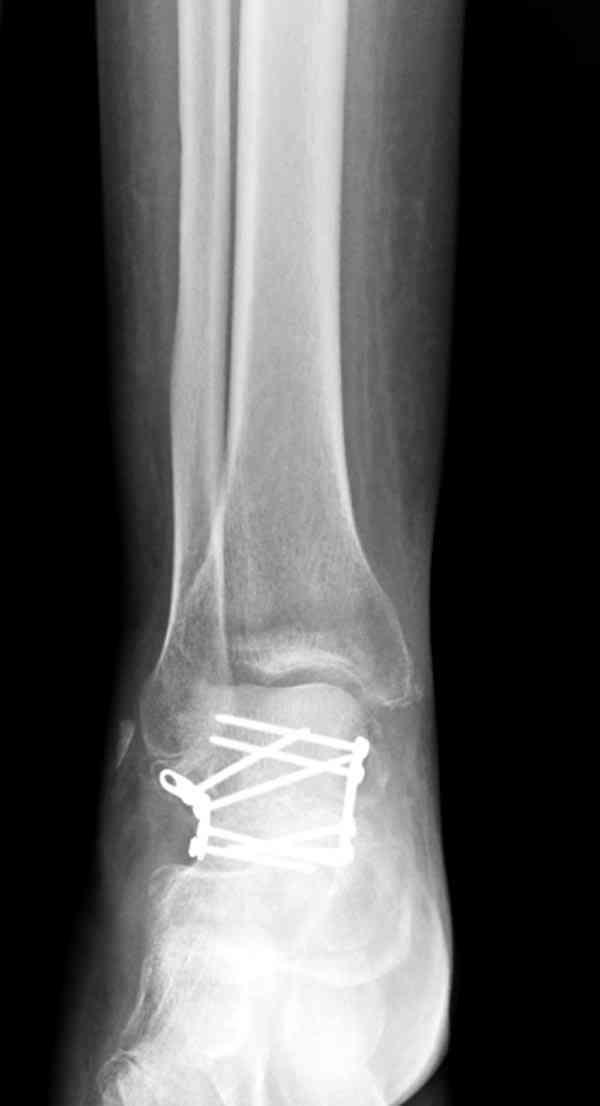

Случай с множественным оскольчатым переломом тарана оперированный из двойного доступа.

Через 2 мес.: